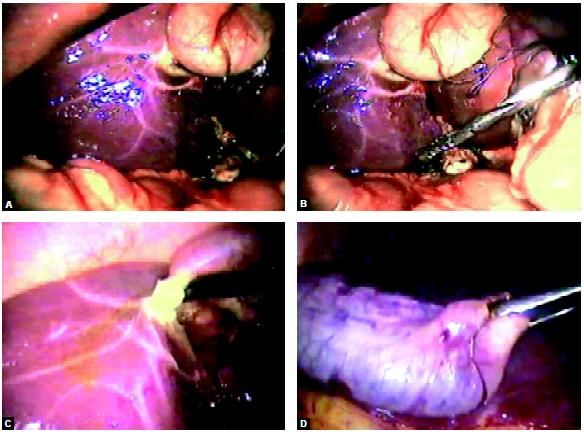

Laparoscopic cholecystectomy is the gold standard for the treatment of gallstone disease. The operation is routinely performed using four or three ports of entry into the abdomen. At Laparoscopy Hospital we frequently perform cholecystectomy by a two-port method using a modified extracorporeal knot. With this technique, we can give traction over the gallbladder in any direction for proper exposure. This new innovative two-port method of gallbladder removal can be used only for simple uncomplicated cholelithiasis cases by an experienced surgeon, but it has a definite advantage over conventional three or four-port cholecystectomy in two-port cholecystectomy fundus is retracted by the help of strategically passed suture. Once the proper exposure of the cystic pedicle is achieved Maryland is used for dissection.

Port position for two-port cholecystectomy

Fundus is retracted up with the help of needle and thread passed through intercostals space under vision

Another Vicryl is applied over Hartsman pouch to provide anterolateral traction. Any leak from the gallbladder is irrigated and sucked nicely with the help of suction irrigation instrument

Dissection of the cystic pedicle is performed by Maryland